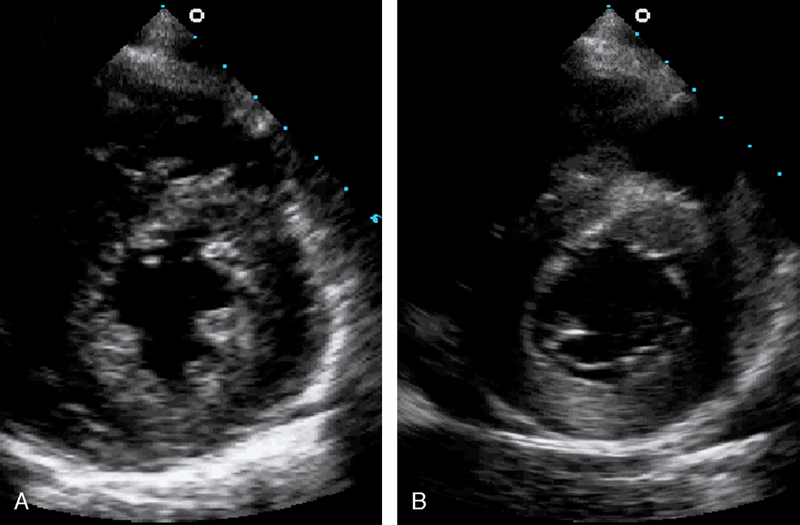

فحوصات تشخيصية لبعض امراض القلب والشرايين التاجية